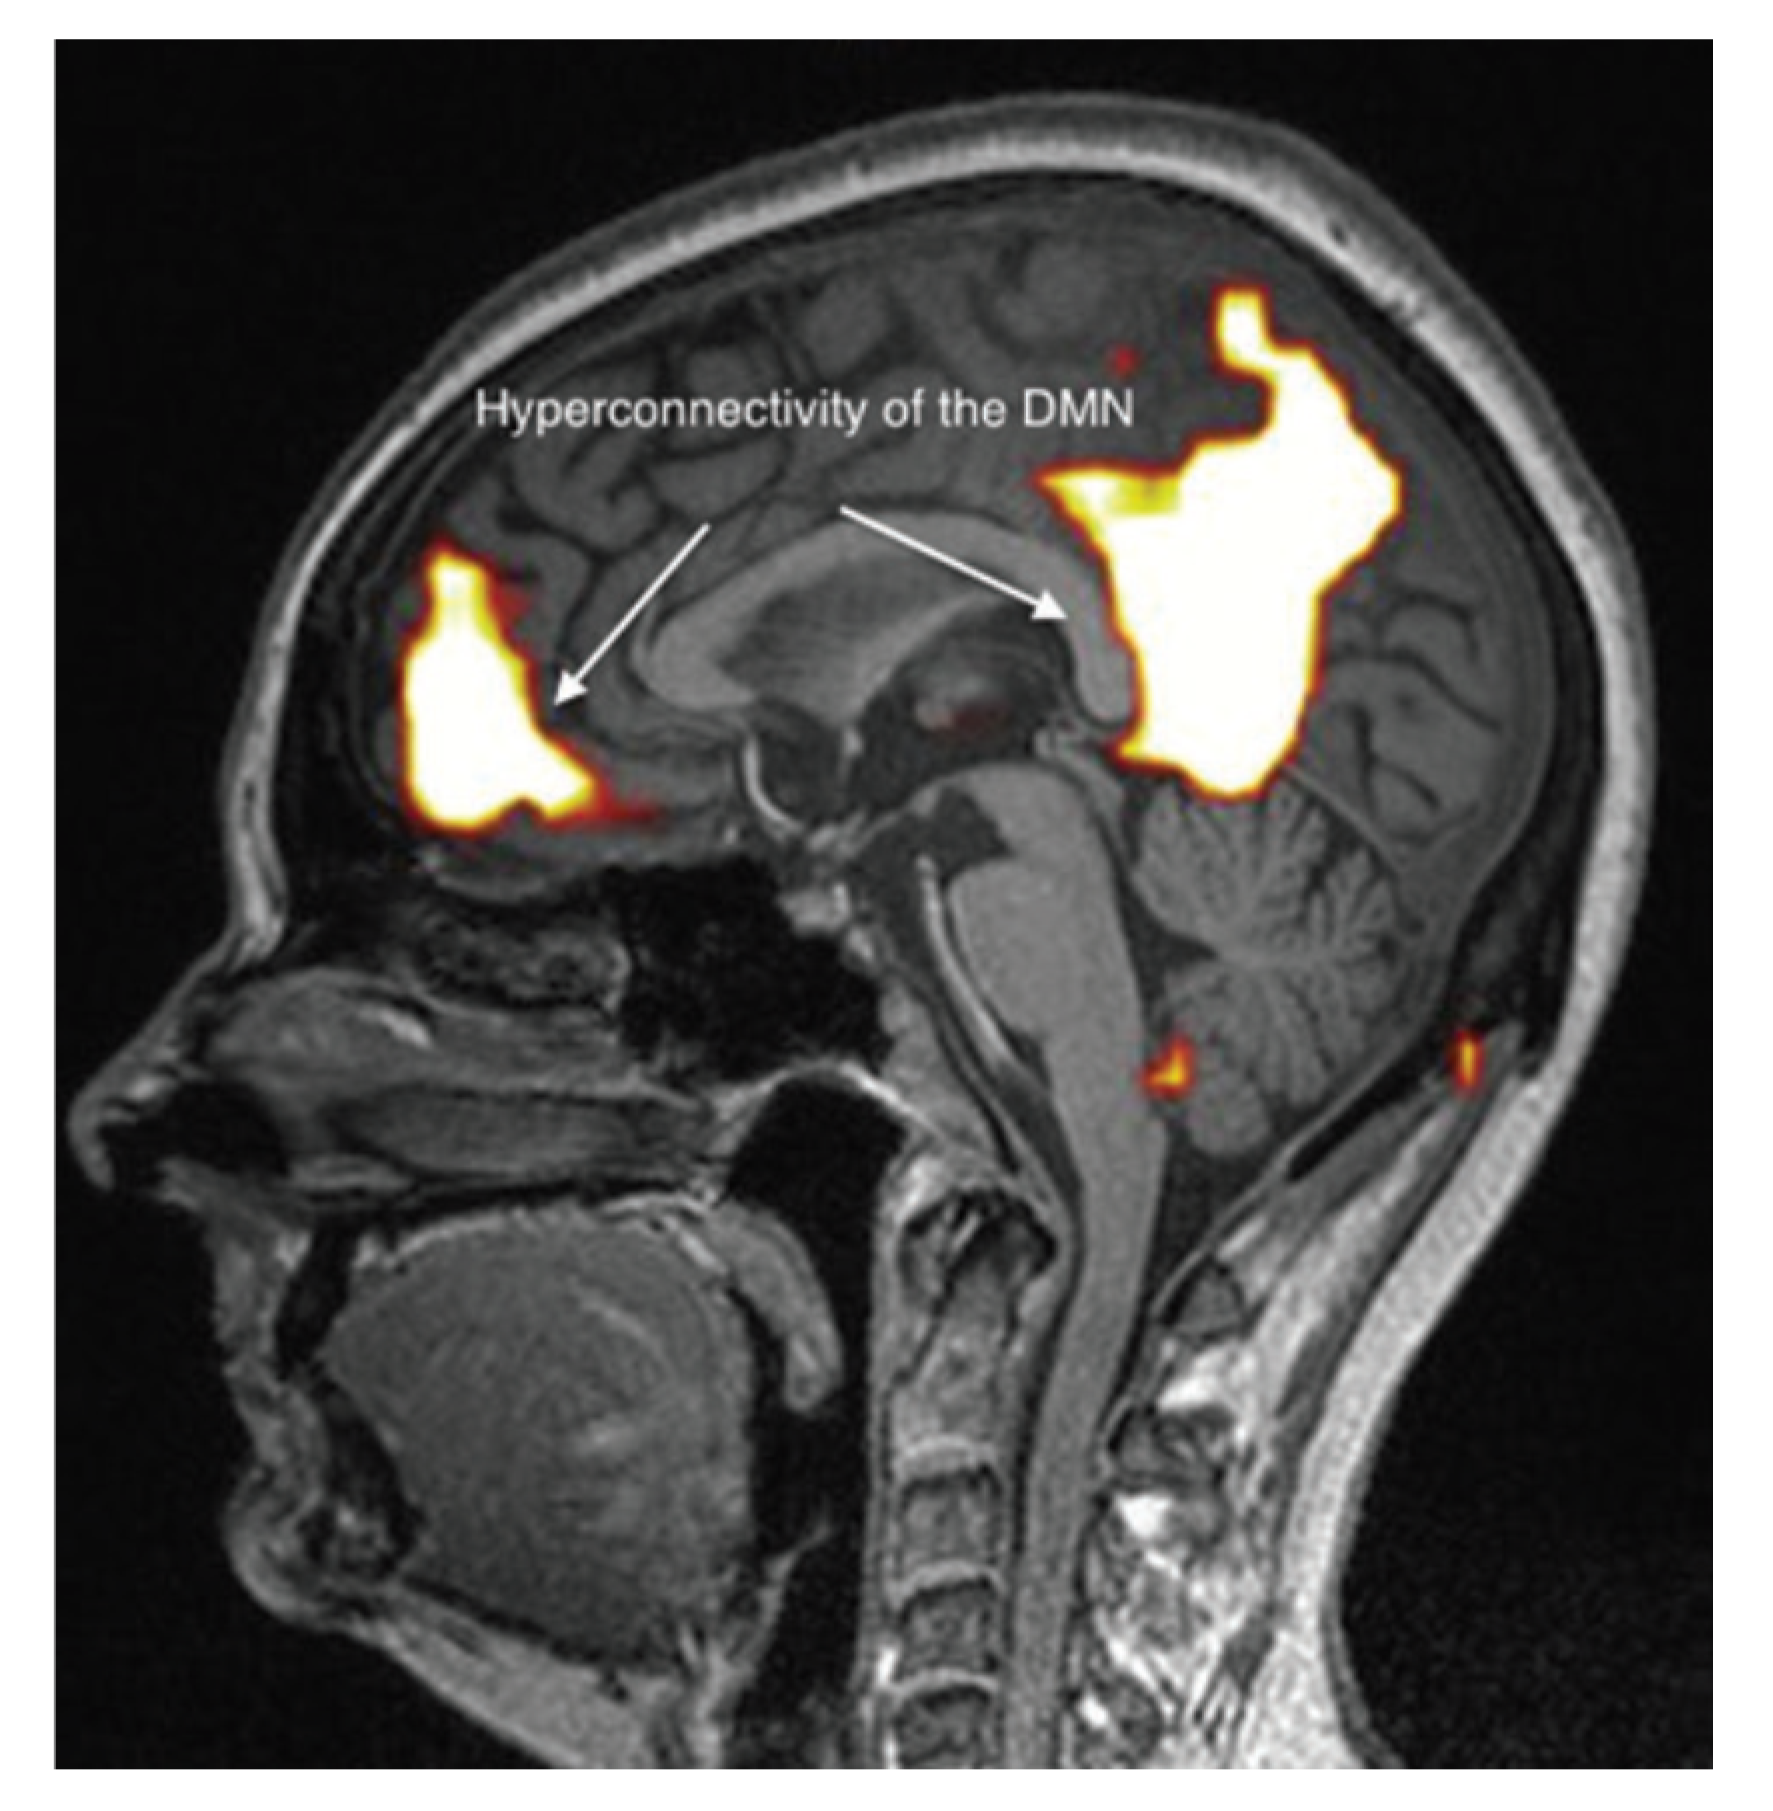

It appears, however, that these brain abnormalities are not restricted to the limbic system and the thalamus, since, by using TDU as indicated above, we showed that, in EHS and/or MCS patients, BBF in the middle cerebral arteries may be abnormal. Moreover, by using functional MRI (fMRI) in EHS patients exposed chronically to extremely low-frequency (ELF) radiation, regional BBF changes were also reported by Heuser and Heuser, but mainly in the frontal lobes, as an abnormal default mode network (DMN) (particularly as hyper-connectivity of this DMN), in association with a decrease in cerebral BBF and metabolic processes in the two so far individualized fragment hyper-connected components [31]. For example, in Figure 4, abnormal DMN is represented with fragmented hyper-connectivity of the anterior component and posterior component, which may lead to decreased BBF and/or metabolism in the bi-frontal lobes.

Figure 4.

Abnormal functional MRI brain scan in patients complaining of EHS after long-term exposure to EMF, according to Reference [31].